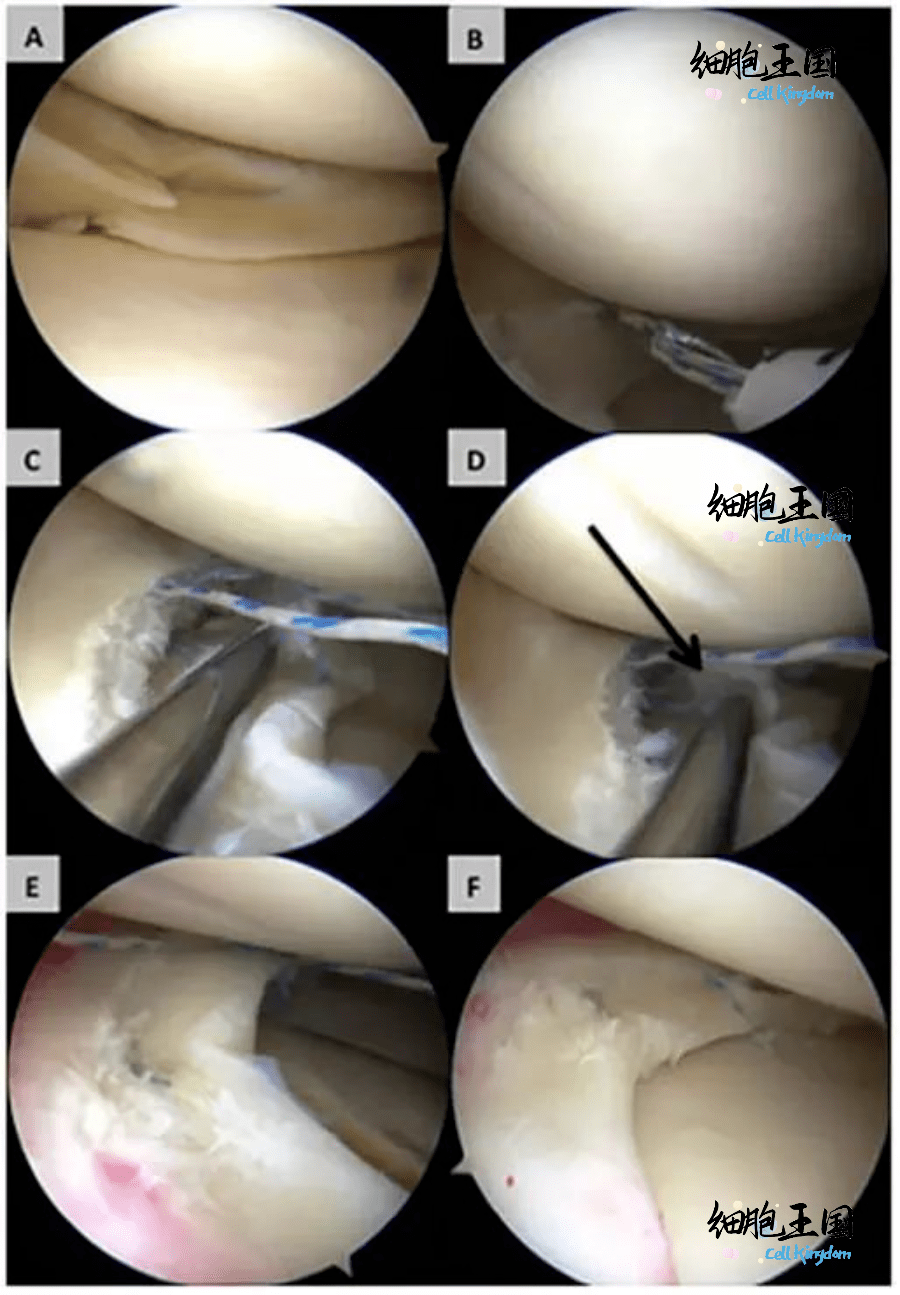

关节镜下外侧半月板修复术

图片尺寸1435x1200